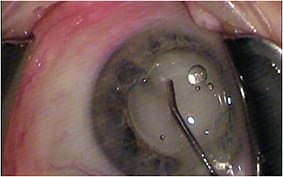

Immediately after injecting the TriMoxi+vancomycin mixture into the anterior vitreous through the zonules, the surgeon withdraws the cannula.

COURTESY: JEFFREY T. LIEGNER, MD